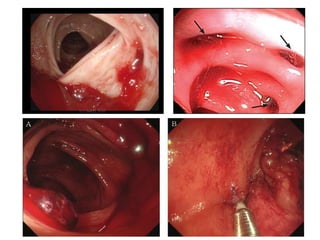

• Endoscopy

• Initial diagnostic method of choice

• IDs cause up to 90%

• Endoscopy for localisation & haemostasis